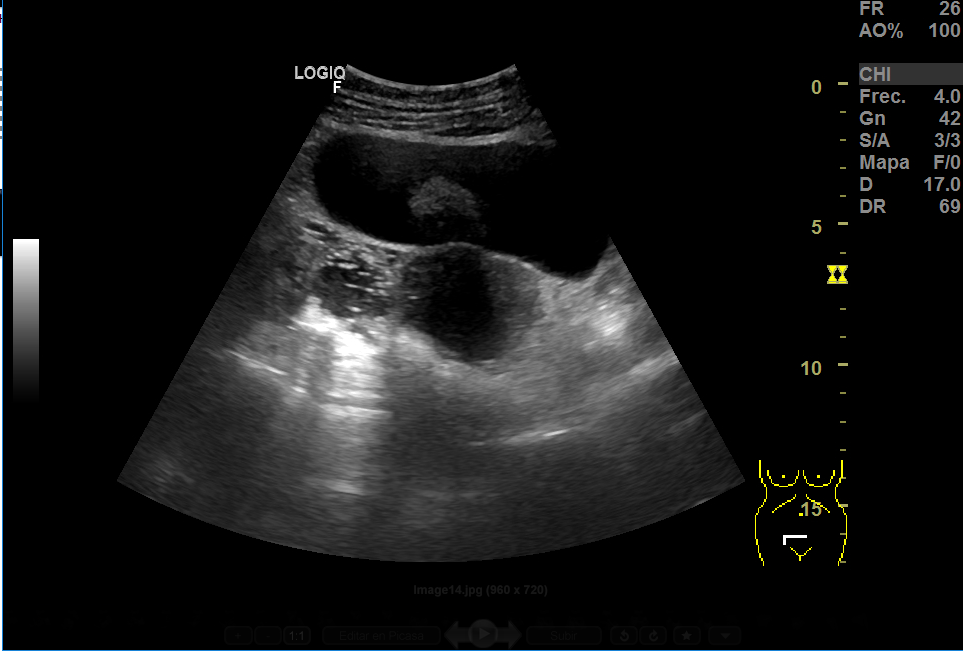

Realizamos una ecografía en el centro de salud y objetivamos, adyacente a útero, una imagen heterogénea de gran tamaño (15x8 cm), con vascularización, que podría corresponder a un mioma gigante. En anejo derecho, imagen redondeada de aproximadamente 3 cm en cuyo interior aparecen líneas hiperecogénicas en un fondo hipoecoico que podrían corresponder a teratoma, sin descartar otra patología. Ante la duda, derivamos a ginecología.

En ginecología, repiten ecografía, esta vez transrectal (paciente sin RS). Confirman mioma de gran tamaño y masa anexial bilateral, por filiar.

La RMN confirma la masa fibrótica de 11x8x10 en relación con mioma pediculado. Imágenes en la línea medida de fondo saco de Douglas de 55x46 y otra de 37x36, bien delimitadas, hiperintensas, compatibles con teratomas.

La anatomía patológica ha confirmado el dx de mioma y de teratomas bilaterales.